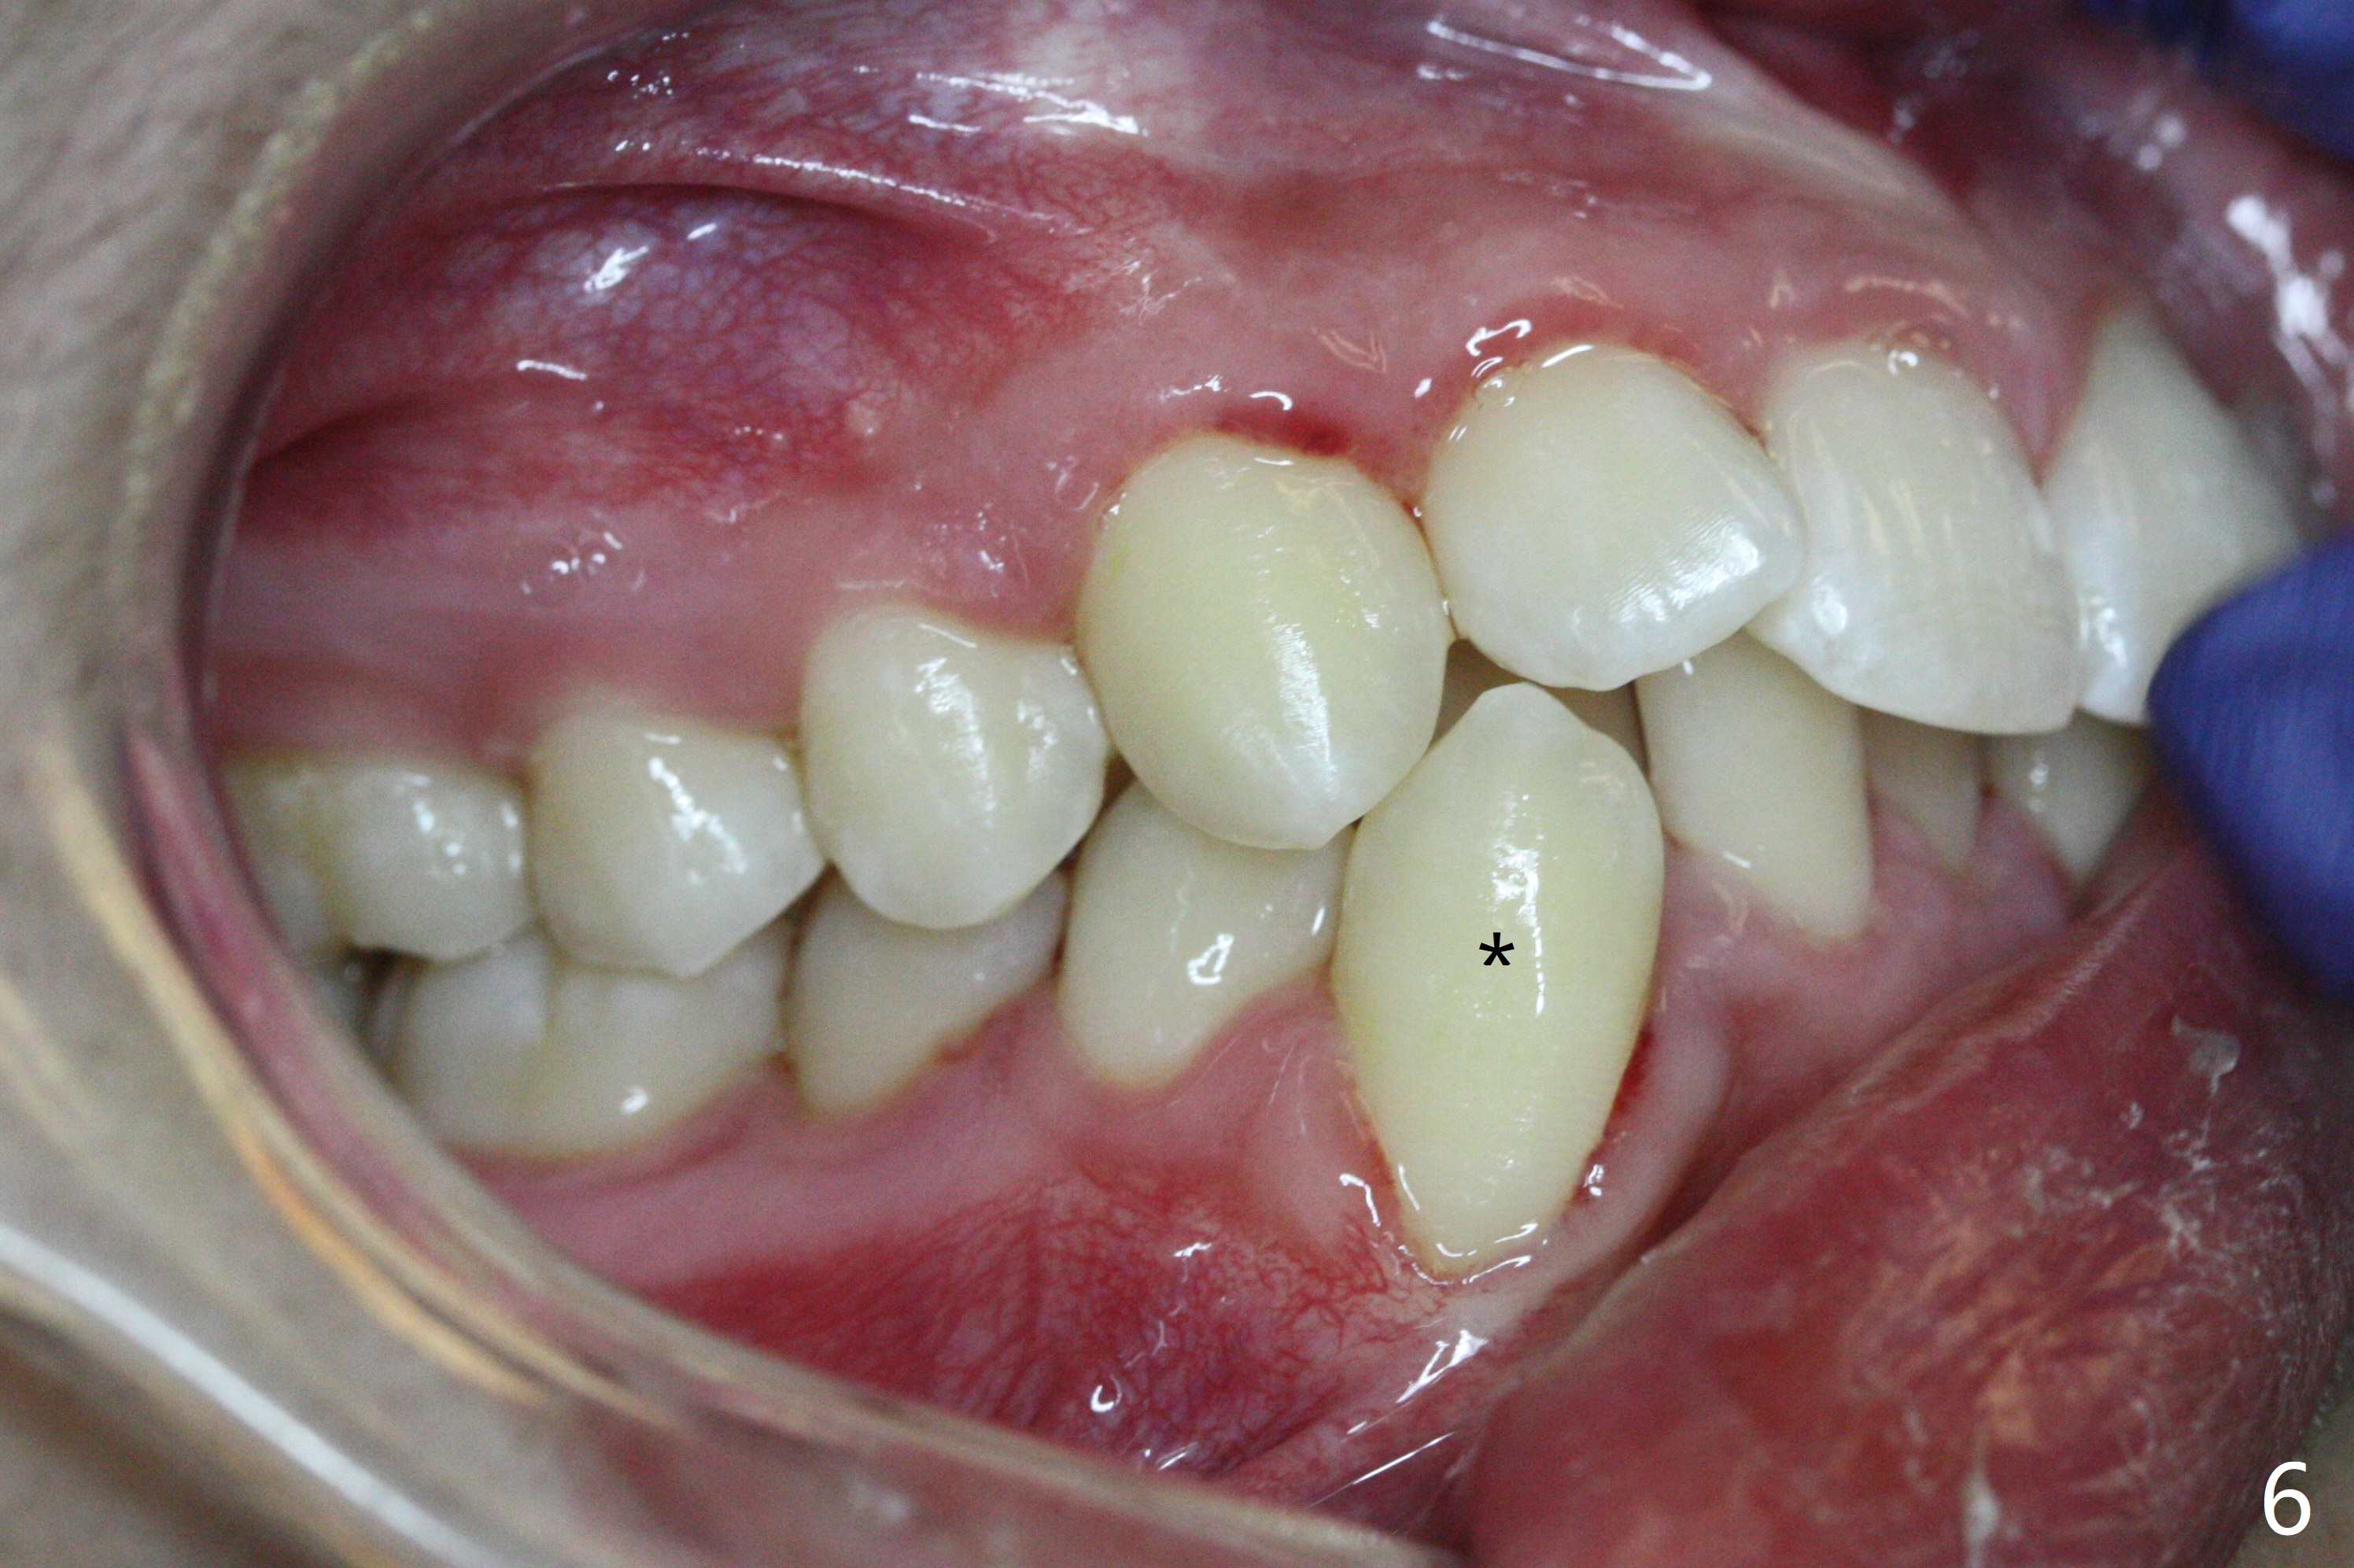

A 15-year-old man requests orthodontic treatment and agrees with extraction.  It appears that the maxilla is more protrusive than the mandible (Fig.1-4, 6,8).  The lower right canine has severe gingival recession (Fig.6,7,10).  Can we extract U4s and LR3 or 2 instead, considering relatively normal alignment in LL (Fig.8, occlusal view)?

Hi Xin, If the patient is protrusive enough (and Class I) to warrant extraction therapy, you will extract one dental unit in each quadrant, normally all four 4s. The wild card in this case is the LR3 recession and the root length being no better than the LR4. So, I would consider extraction of U4s, LL4, and LR3. Bottom line, your LR4 becomes your canine in this case.  Tim Monday, February 5, 2018 9:15 AM

In fact, extraction of LR3 is easier than the other three, because of its labial socket (Fig.10 * (loss of the labial plate), as compared to Fig.9).  Nevertheless, the root of LR3 is the longest (Fig.11).